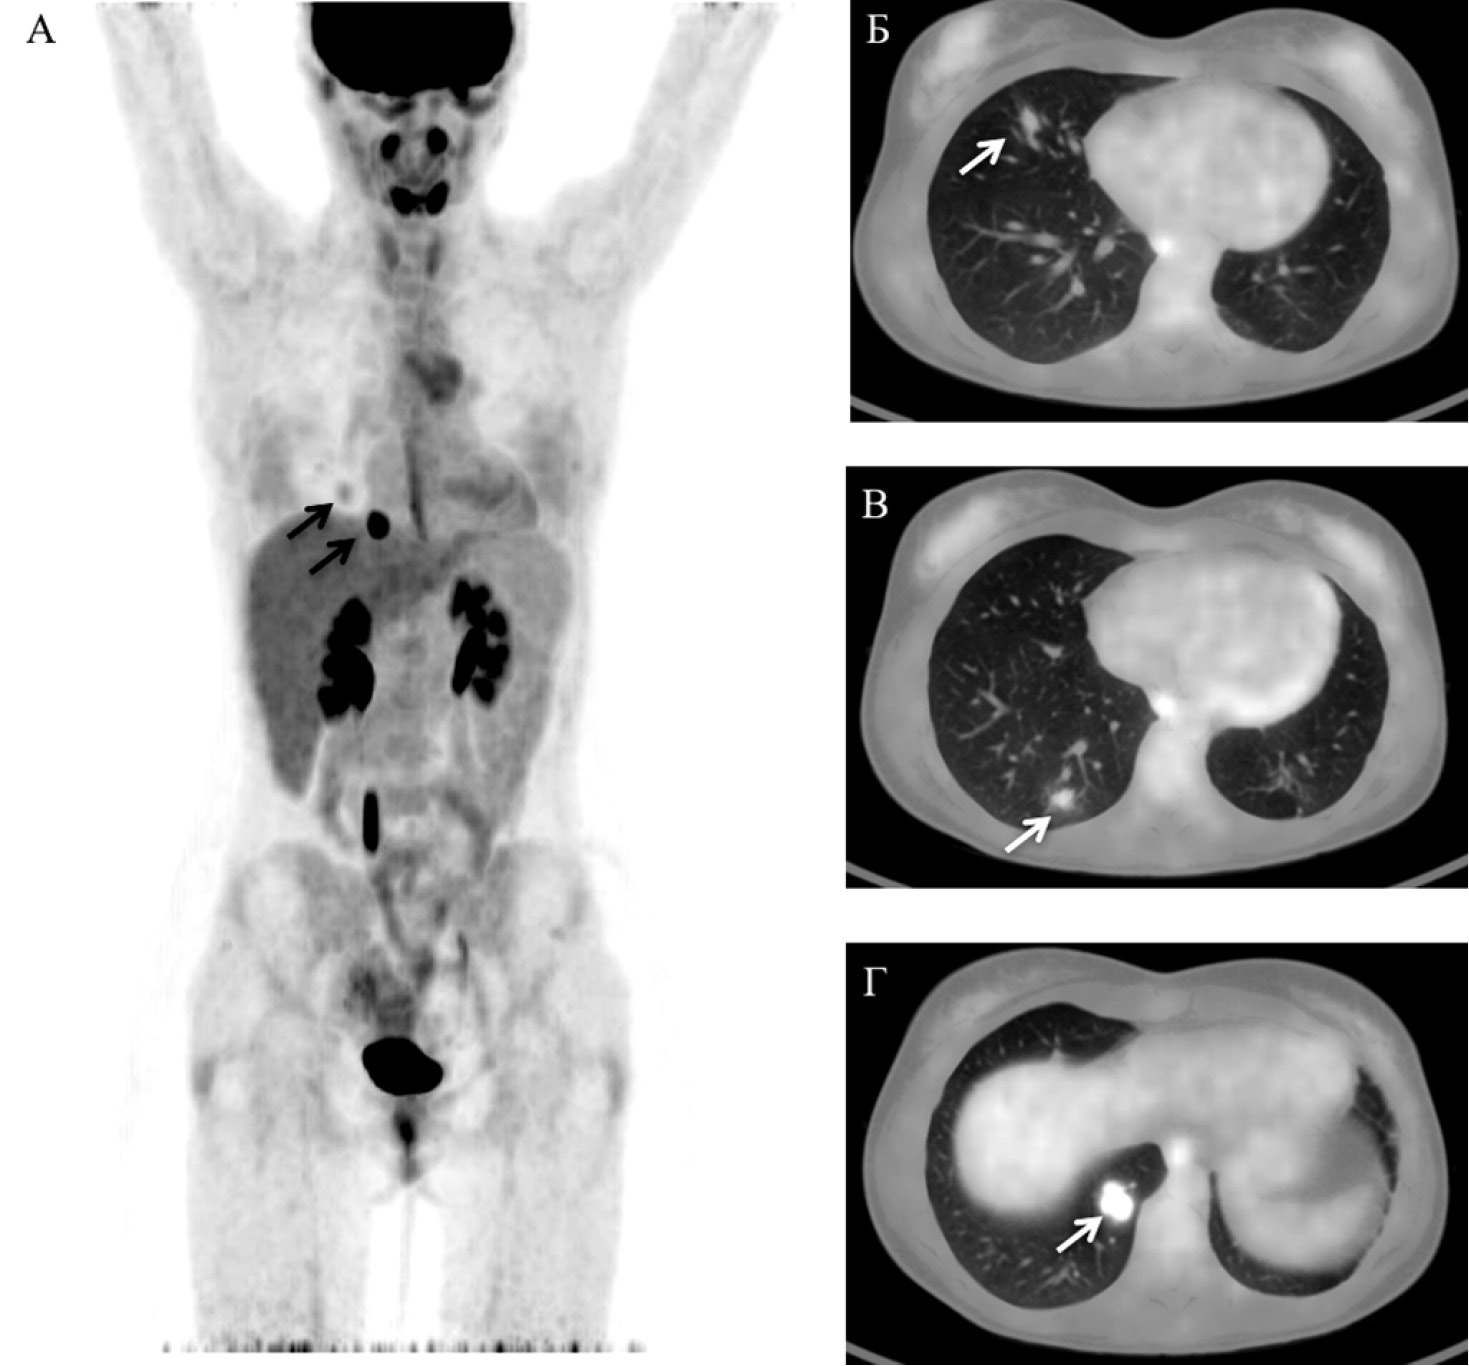

При динамическом наблюдении за уровнем β-ХГЧ через 6 мес после окончания химиотерапии зафиксировано его постепенное увеличение. В декабре 2016 г. в связи с этим выполнено обследование в «НМИЦ онкологии им. Н.Н. Блохина» (КТ органов грудной полости и экспертное УЗИ органов брюшной полости и малого таза): новых очагов опухоли не обнаружено, в лёгких – положительная динамика в виде уменьшения размеров и количества ранее определяемых метастазов. Уровень β-ХГЧ на момент обращения составлял 231 мМЕ/мл. Для уточнения локализации рецидивной опухоли выполнена ПЭТ/КТ с 18F-ФДГ. По результатам исследования установлено патологическое накопление 18F-ФДГ до макс SUV 1,31–5,68 в следующих образованиях правого лёгкого: в S5 размерами 1,3×1,0 см, в S9 размерами 0,9×0,6 см, в S10 размерами 1,9×1,3 см (рис. 2).

Рис. 2. Позитронная эмиссионная томография (MIP-реконструкция) во фронтальной проекции (А), совмещённые ПЭТ/КТ-изображения (Б, В, Г) в аксиальной проекции. Стрелками указаны очаги патологического накопления 18F-ФДГ в образованиях правого лёгкого